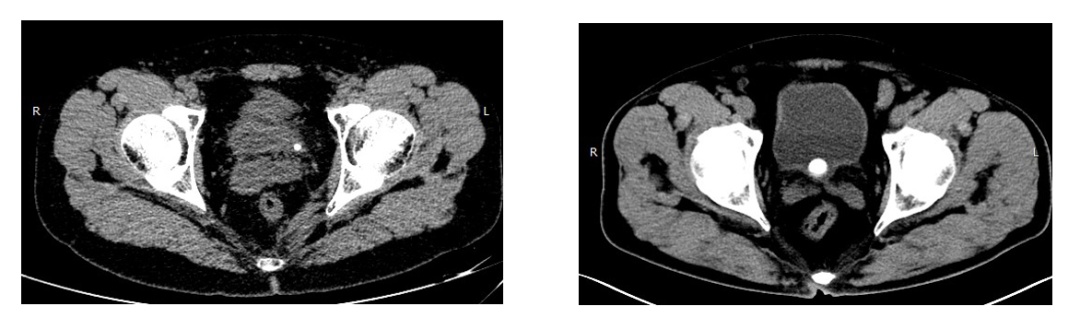

输尿管末端的结石,结石卡在输尿管与膀胱之间;膀胱结石,结石在膀胱里来回滚动,两者均会引起尿频、尿急的症状。

膀胱三角区的肿瘤也会导致患者一直有尿急的感觉。老年男性患者的长期前列腺增生引起的梗阻会导致膀胱结构的改变,膀胱增厚,导致膀胱粘膜敏感以及不自主收缩,在排尿困难的同时也会引起尿频、尿急的症状。